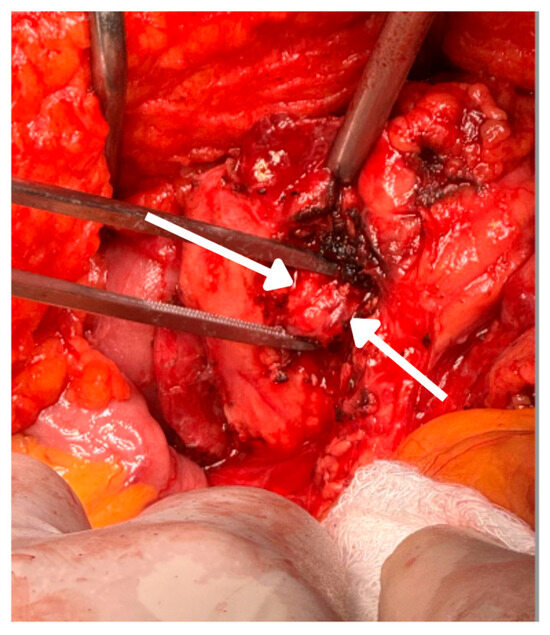

In March 2024, the patient underwent partial pancreatectomy. Intraoperatively, a firm 1 cm nodular lesion was identified on the anterior surface of the pancreatic uncinate process, lateral to the mesenteric vessels. The lesion was resected, and the biopsy of a frozen section confirmed a neuroendocrine tumor (Figure 3).

Figure 3.

Pancreatoduodenectomy: intraoperative view of the pancreatic uncinate process showing exposed tissue following surgical resection. The arrows discreetly indicate the specific area of the surgical bed corresponding to the resection of an insulinoma. Hyperemic tissue characteristics and cauterized margins are observed, indicating adequate hemostatic control during the procedure. This finding is consistent with pancreatoduodenectomy.